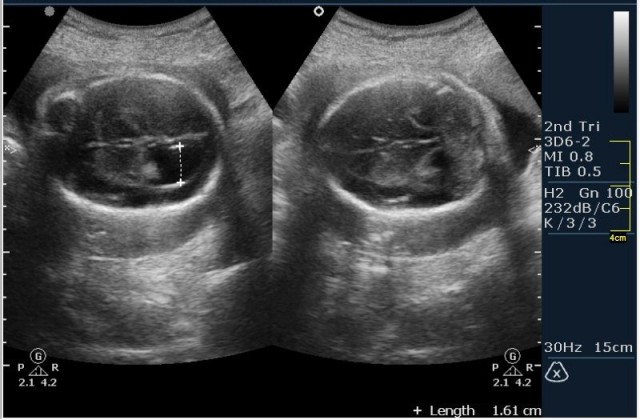

1.Вентрикуломегалия/гидроцефалия (на сонограмме №1 размер задних рогов боковых желудочков 16мм при норме до 10 мм включительно;

На сонограммах головы плода визуализаируется гифдроцефалия, патогенетически связанная со спинномозговой грыжей (менингомиелоцеле) представленная в 2D и 3D режимах. В режиме Skeleton не удалось получить "картинку презентационного качества", плод начал сильно вертется; но рекоммендация очень грамотная :idea: , спасибо за ваш пост!